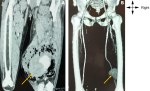

Diagnostic assessment: the electrocardiogram showed sinus rhythm with polymorphic ventricular extrasystoles. Angiography of the lower limbs, including the coronal and reconstructive sections shown in Figure 2 A and B, revealed an aneurysm of the popliteal artery with perianeurysmal muscle abscesses. The complete blood count showed anaemia with a haemoglobin level of 9.6 g/dl and leukoneutropenia at 2.9,000/ml. The viral load was 2.5 Log/ml. The CD4 count was 250/mm³. Pathological examination of the excised mass revealed a eumycetoma.

Figure 2: angiography of the pelvic limbs with IV injection of iodinated contrast medium: A) at the arterial phase in coronal and frontal; B) reconstructions showing a vascular mass, with a large haematoma and perianeurysmal abscesses, clearly limited to the appearance of a mycotic pseudoaneurysm developed at the expense of the right popliteal artery